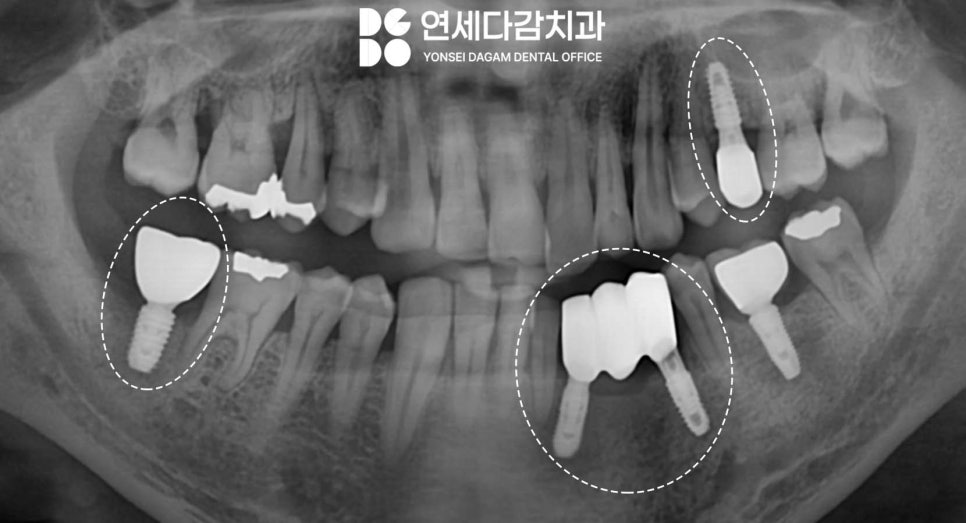

치료 과정

가락시장역 치과 에서

앞에서 언급한 문제의 부위들을

골이식과 동시에 임플란트 식립을

진행했습니다.

세심하고 정밀한 작업을 통해

다행히 고정력을 잘 얻어낼 수 있었습니다.

아무래도 소실된 만큼

많은 양의 뼈이식이

진행되었기 때문에,

충분한 골융합을 위한

치유 기간이 필요했습니다.

식립한 고정체를 잇몸 속에

묻어두고 충분한 치유 기간을 기다리며

골의 밀도를 주기적으로 확인했습니다.

정기적인 검사를 통해

골 유착 과정이 제대로

이루어진 것을 확인하고 나서

다음 단계를 마저 진행했습니다.